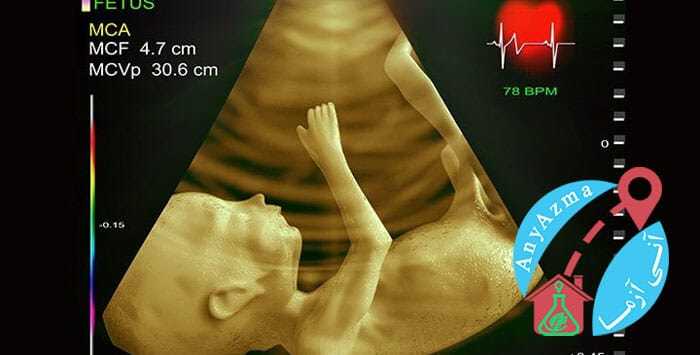

- سونوگرافی NT (شفافیت گردن جنین): در این سونوگرافی تخصصی، متخصص مقدار مایع تجمع یافته در پشت گردن جنین را اندازهگیری میکند. افزایش ضخامت این ناحیه (Nuchal Translucency) میتواند نشانهای از افزایش ریسک برخی ناهنجاریهای کروموزومی باشد. در این سونوگرافی، وجود استخوان بینی جنین (Nasal Bone) نیز بررسی میشود.

تست های غربالگری بارداری بوسیله سونوگرافی و آزمایش خون انجام می شود. برای آزمایش خون در این تست نیاز به شرایط خاصی نیست و طبق تشخیص پزشک در زمان مشخص خود باید انجام شود. انجام سونوگرافی نیز به صورت شکمی بوده و شرایط آن همانند سونوگرافی های معمولی است. یعنی باید قبل از انجام آن مثانه پر باشد. این سونوگرافی خطری برای مادر و جنین نخواهد داشت.

بله! پس از بارداری معمولا سونوگرافی های معمولی و تشخیصی برای خانم باردار توسط پزشک تجویز می شود. در سونوگرافی های معمولی فرآیند بارداری ، رشد و وضعیت جنین مورد بررسی قرار می گیرد. در ابتدای بارداری یک سونوگرافی از خانم باردار انجام می شود تا تایید شود بارداری در داخل رحم ایجاد شده است یا خیر؟

در مرحله بعد سونوگرافی در هفته های 12 ، 22 و 32 انجام می شود. در صورتی که مادر مبتلا به فشار خون، دیابت و بیماری خاصی باشد تعداد سونوگرافی افزایش پیدا می کند. استفاده مکرر از سونوگرافی در دوران بارداری توصیه نمی شود چون در هر حال از اشعه برای انجام این کار استفاده می شود. در تست های غربالگری بارداری استفاده از سونوگرافی بخشی از روند تشخیص است و بنابراین باید در کنار آزمایش خون انجام شود. اگر شرایط حادی دارید می توانید برای سونوگرافی در منزل از خدمات آنی آزما استفاده کنید.